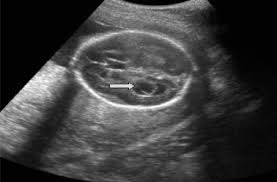

Here are common soft markers that show up in the second-trimester ultrasound. Mid-trimester soft markers have been linked with Down syndrome and other aneuploidies. Thickened nuchal fold echogenic bowel shortened femur shortened humerus pyelectasis and absent or hypoplastic nasal bone.

Ultrasound is a key component of aneuploidy screening. Ultrasonically echoreflective bowel bright gut short femurs clinodactyly of the fifth digit and oddly shaped heads have all been identified as soft markers associated with an increased risk of trisomy. Soft markersDown syndrome.

Certain features detected during a second trimester ultrasound exam are potential markers for Downs syndrome and they include dilated brain ventricles absent or small nose bone increased. But there is nothing to worry about and my child is perfectly normal Becauese my first-trimester scan and blood test were both normalBUT I need to make an appointment with a genetic. Approximately 30 of babies with Down syndrome have detectable abnormalities on the mid-trimester ultrasound 1.

Down Syndrome can include cardiovascular central. A review on the various soft markers identified for the detection of down syndrome from the first and second trimester ultrasound fetal images has been made. In this low risk population soft markers were found in 59 of fetuses at second trimester ultrasound.

There are specific characteristics identified during an ultrasound exam in the second trimester of a womans pregnancy that are possible indicators for Downs syndrome. Both major structural abnormalities and minor soft markers can be detected by ultrasound in fetuses affected with aneuploidies. There are many other prenatal screening tests available with better detection rates for Down syndrome than the mid-trimester ultrasound.